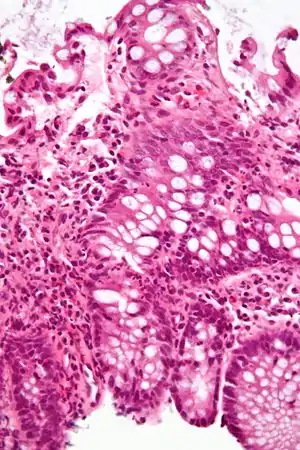

| A micrograph demonstrating cryptitis, a microscopic correlate of colitis. H&E stain. | |

An important investigation in the assessment of colitis is biopsy. A very small piece of tissue (usually about 2mm) is removed from the bowel mucosa during endoscopy and examined under the microscope by a histopathologist. It can provide important information regarding the cause of the disease and the extent of bowel damage.

Lymphocytic colitis